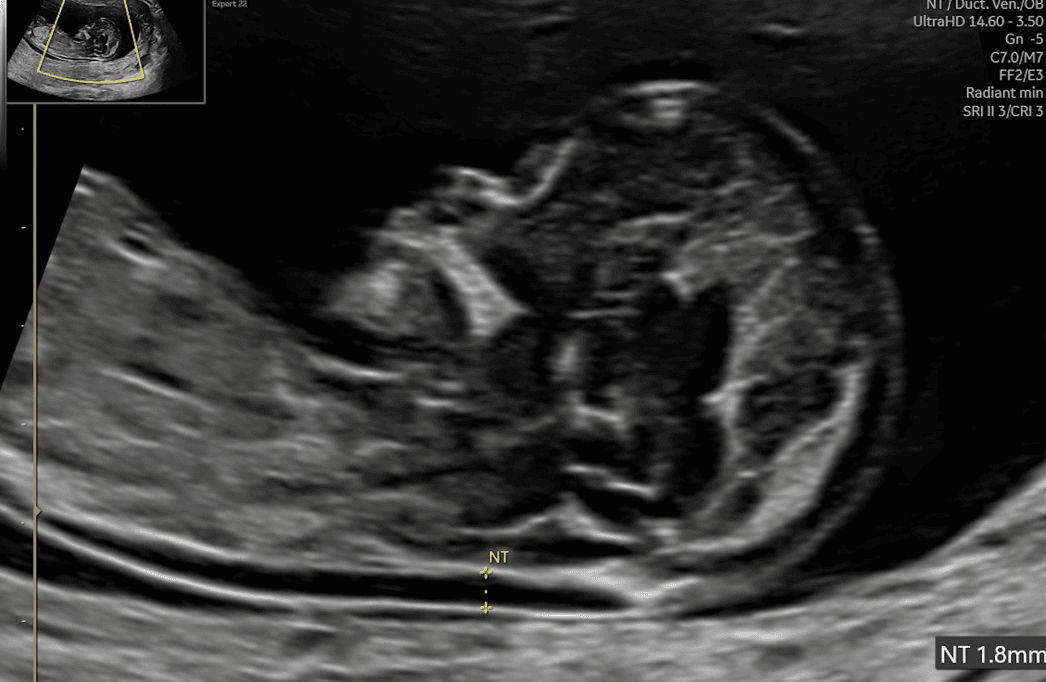

まず初期(妊娠11〜14週)の超音波では、妊娠の生存確認、胎児数の確認、妊娠週数の決定(特にCRL(頭殿長)測定)を行い、多胎であれば絨毛膜性・羊膜性を判定します。また、子宮や付属器、子宮頸部を含む母体側の評価、胎盤位置の確認、さらに妊娠初期に認めうる重大な形態異常の拾い上げも含まれます。必要に応じてNT(後頸部透亮像)の測定など、染色体異常リスク評価に関連する計測も同時期に実施されます。

超音波検査でみる赤ちゃんの姿:丸の内の森レディースクリニック提供